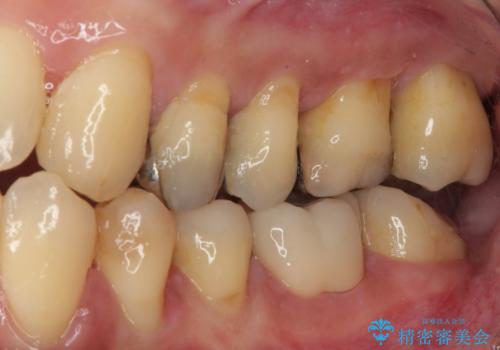

拡大鏡視野下でメタルインレー、虫歯を除去しオールセラミッククラウンに適した形に整えました。

歯と歯茎の間に圧排糸と言われる糸を入れてシリコーン印象材にて型どりをしました。

審美面、機能面共に満足していただけました。

順次、後ろにある不適合のメタルインレーの部位をやり替えていく予定です。